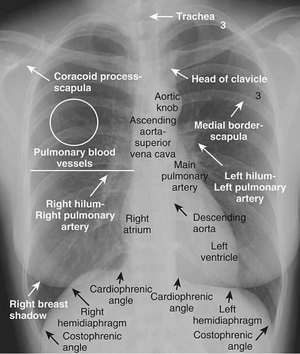

Chest x-ray :- Practical at College (Dayanand Medical College and hospital) The heart is a muscular organ in most animals, which pumps blood through the blood vessels of the circulatory system. Blood provides the body with oxygen and nutrients, as well as assists in the removal of metabolic wastes. In humans, the heart is located between the lungs, in the middle compartment of the chest.